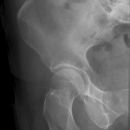

Hüfte axial nach Lauenstein

Indikation

Epiphysioloysis capitis femoris, M.Perthes bzw. Hüftkopfnekrosen anderer Ätiologie.

Darstellung des Schenkelhalses ohne Verkürzung. Keine Bedeutung für die traumatologische Diagnostik, hier a.p.- und axiale Aufnahme als Basisdiagnostik! Keine überlagerungsfreie Beurteilung des Azetabulums möglich!

Beurteilungskriterien

- Femurkopf (Entrundung, Kondensation, Abrutschen?) und Schenkelhalskontur

- Trochanter major (teilweise über Schenkelhals projiziert) und minor